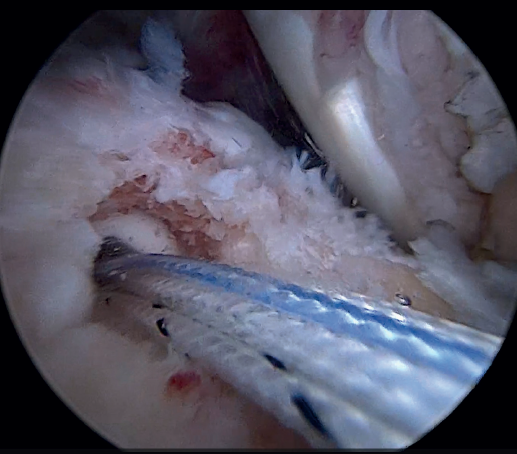

The glenoid origin of the LPB is preserved at all times. In the anterolateral zone of the greater tuberosity, we implant an anchor loaded with three sutures (FiberTak® 2.6 mm, Arthrex, Naples, FL, USA), more medial to the reflection zone of the LPB. To ensure correct guidance at implantation, we create a superolateral accessory portal without a cannula, close to the limit of the acromion.

Using penetrating forceps through the anterior portal, the surgeon penetrates the LPB and retrieves one of the suture threads, performing a self-locking Lasso suture in the same step. This is done with two of the three anchoring threads to ensure a correct LPB grip to the footprint of the greater tuberosity and that the tendon does not fray; we do not cut the two threads after knotting (Figures 4, 5 and 6). We also consider it very important to apply the biceps tendon, keeping it as flat and anatomical as possible, avoiding twisting or excessive distension of the tendon. Subsequently, a tenotomy of the LPB distal to these sutures is performed (Figure 7), thus allowing the LPB to function as a superior capsular reconstruction, restricting the ascent of the humeral head.